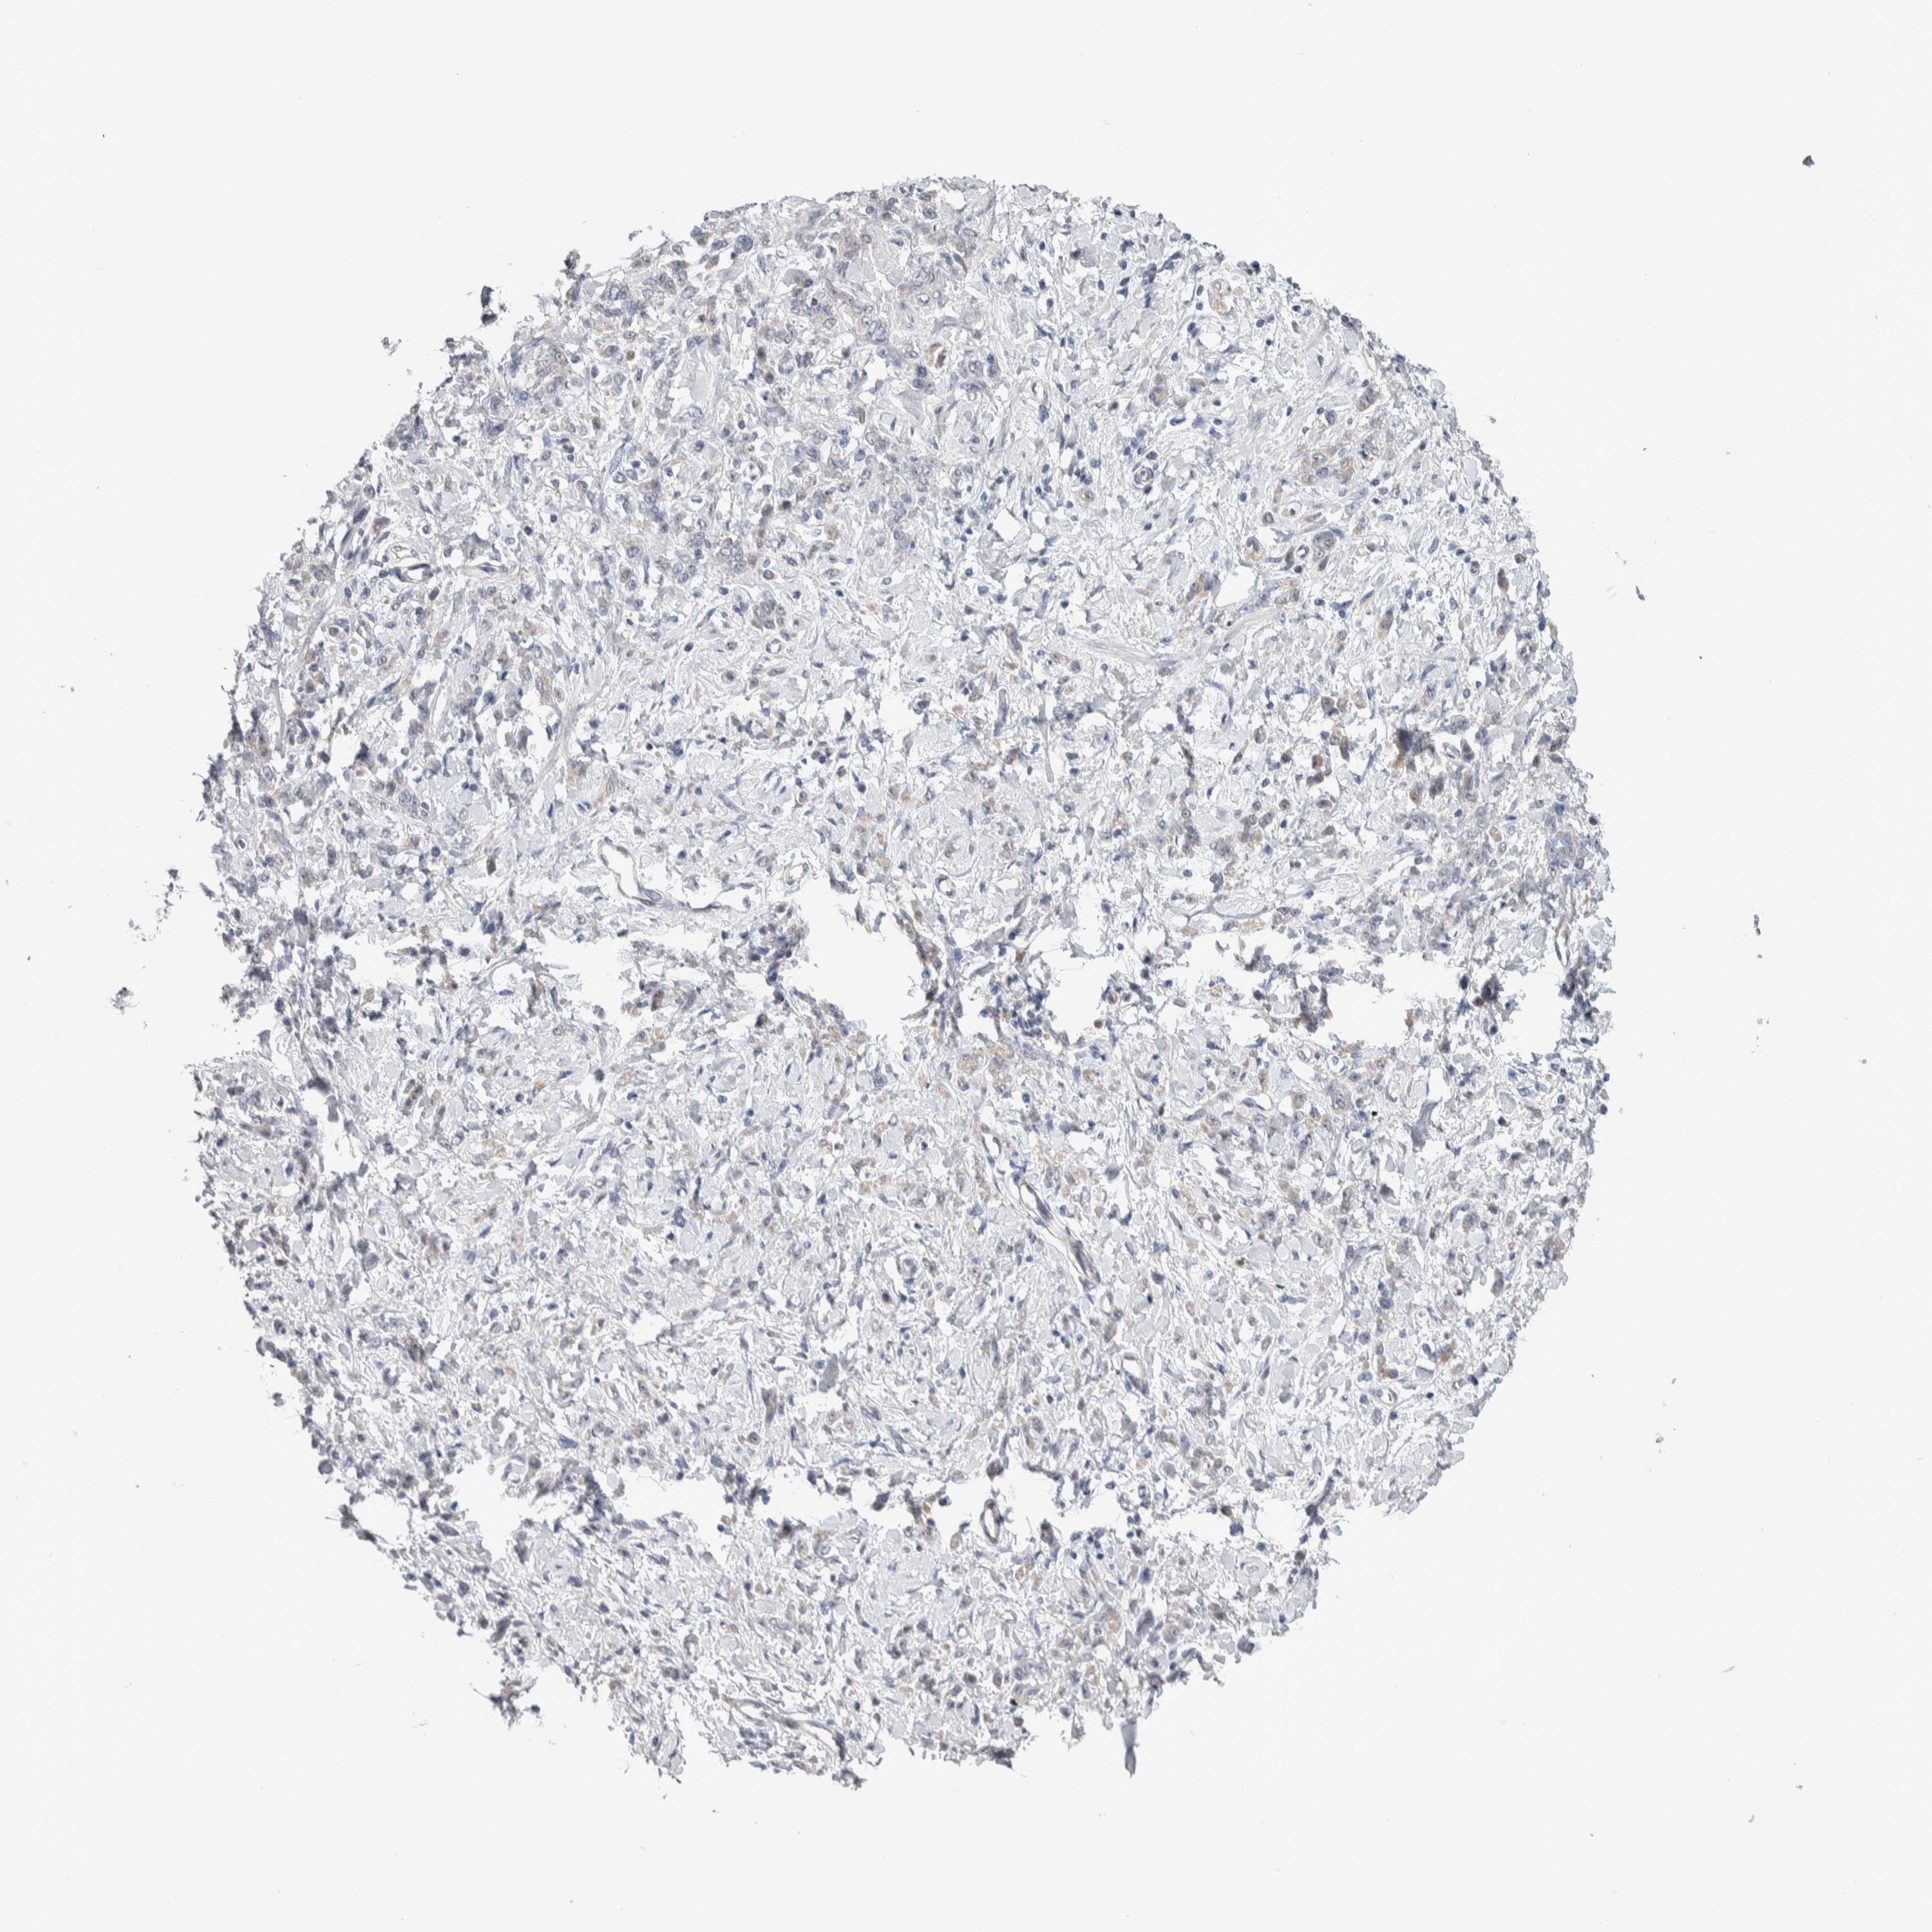

STOMACH CANCER - Protein expressioni

A mouse-over function shows sample information and annotation data. Click on an image to view it in a full screen mode. Samples can be filtered based on level of antibody staining by selecting one or several of the following categories: high, medium, low and not detected. The assay and annotation is described here.

Antibody stainingi

Antibody staining in the annotated cell types in the current human tissue is reported as not detected, low, medium, or high, based on conventional immunohistochemistry profiling in selected tissues. This score is based on the combination of the staining intensity and fraction of stained cells.

Each image is clickable and will lead to virtual microscopy that enables deeper exploration of all samples and also displays staining intensity scores, fraction scores and subcellular localization as well as patient and tissue information for each sample.

Antibody HPA024432

Staining

High

Medium

Low

Not detected

Intensity

Strong

Moderate

Weak

Negative

Quantity

>75%

75%-25%

<25%

None

Location

Nuclear

Cytoplasmic/membranous

Cytoplasmic/membranous,nuclear

Adenocarcinoma, NOS